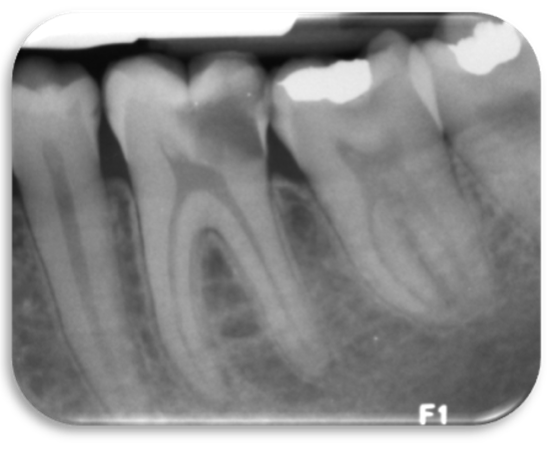

The survey content included a description of a clinical scenario of a patient with shooting diffuse pain in the lower left quadrant of the mouth that upon examination revealed a carious lesion reaching the pulp of a first permanent molar with no apical radiolucency (Figure 1). The final diagnosis was an irreversible pulpitis with normal apical tissues.

Figure 1. Radiography of a permanent first molar with deep caries used for the clinical scenario